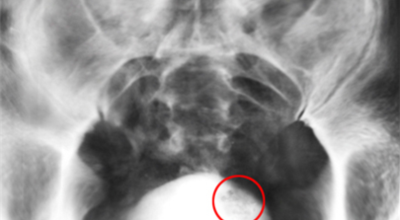

방광암 치료법은 경요도 절제술을 하게 되는데요. 이 후 종양의 개수나 크기, 재발 기간 등에 그렇기 때문에 항암제를 주입하는 등 여러가지 치료를 하게 되는데요. 상황에 그렇기 때문에는 방광 적출술이 필요할 수 있고, 재발이 잦기 때문에 방광암 치료법을 시행하면서도 주기적인 추적 검사를 해야 합니다.